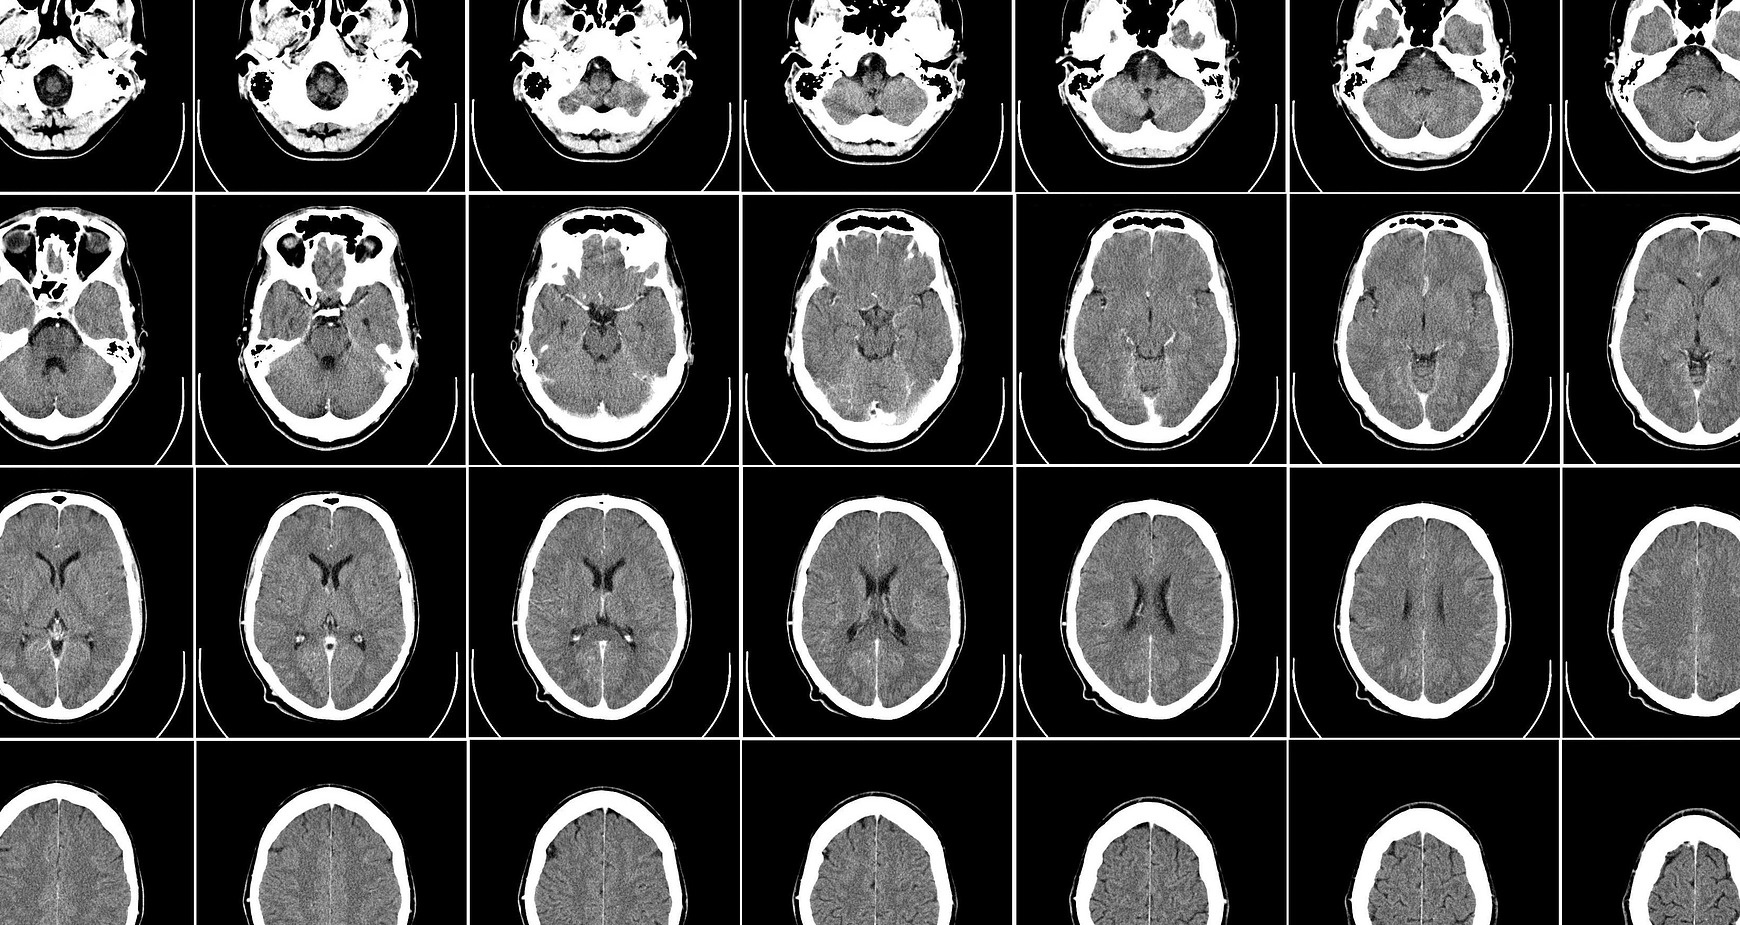

伦敦国王学院的研究人员使用NVIDIA Cambridge-1超级计算机和MONAI打造一个开源合成大脑图像宝库,加速了AI在医疗健康领域的应用。

这位伦敦国王学院的研究人员兼伦敦AI中心的CTO为医疗健康研究人员免费提供了10万张合成大脑图像。这是一个宝库,可以加速人类对痴呆症、衰老或各类脑部疾病的认知。

这种新型AI方法的重要特征是,它可以根据需要制作图像。女性大脑、男性大脑、老年人的大脑、年轻人的大脑、患有疾病或健康的等等,只需插入所需内容,系统就会进行创建。

虽然这些图像是模拟生成的,但非常实用,因为它们保留了关键生物特征,所以外观和运作方式与真实大脑高度相似。

不仅于此,团队还在探索这些模型如何在医学成像模式下(MRI、CAT或PET扫描等)为人体任意部位生成3D图像。